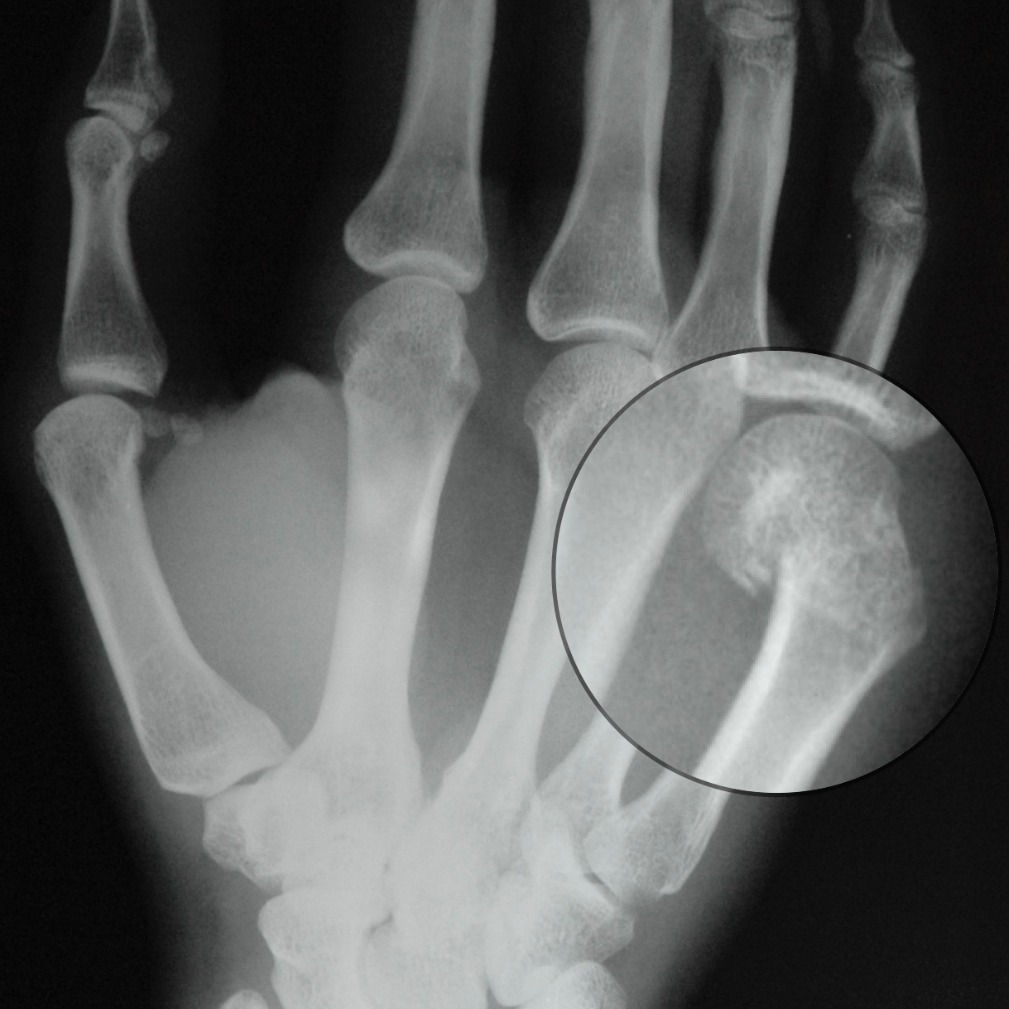

Boxer’s Fracture — Boxer Wrist Injuries we identified 32 nonoverlapping studies involving a total of 4299 hand and wrist injuries. Proper wrapping and padding techniques can significantly reduce the risk of wrist. wrist strengthening for boxing is important to prevent injury, improve accuracy, and increase power. a boxer’s fracture is a fifth metacarpal fracture (the bone that connects your pinkie finger to your. Boxer Wrist Injuries.

FileBoxers fracturelateral xray.JPG Wikimedia Commons Boxer Wrist Injuries Adding a few simple exercises to. a boxer’s fracture is a fifth metacarpal fracture (the bone that connects your pinkie finger to your wrist). prevention of hand injury in boxing centers around 4 main concepts: Proper wrapping and padding techniques can significantly reduce the risk of wrist. boxer’s fracture, wrist sprains/strains, and shoulder injuries may be treated. Boxer Wrist Injuries.

Trauma Xray Upper limb gallery 2 Hand Boxer's fracture Boxer Wrist Injuries boxer’s fracture, wrist sprains/strains, and shoulder injuries may be treated with immobilization, rest, ice,. wrist strengthening for boxing is important to prevent injury, improve accuracy, and increase power. of the hand and wrist injuries sustained by elite boxers across a five year period, carpometacarpal instability (21.6%) and an. we identified 32 nonoverlapping studies involving a total. Boxer Wrist Injuries.